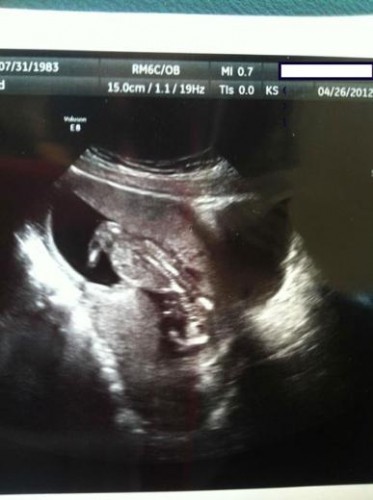

Bebeklerinin bu ilk görüntüsüyle anne-babalar şoke oldu!

El işareti yapan bebek